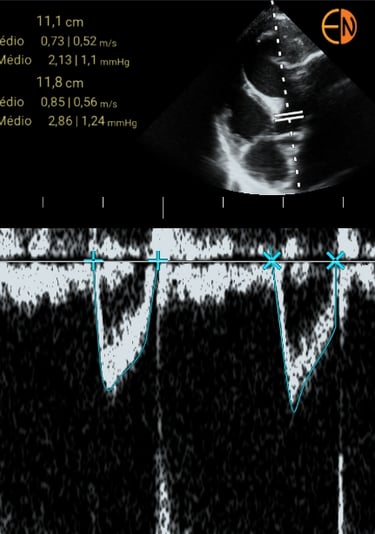

POCUS Cardíaco - medidas: Avaliação quantitativa do débito cardíaco, volume sistólico e função sistólica dos ventrículos.